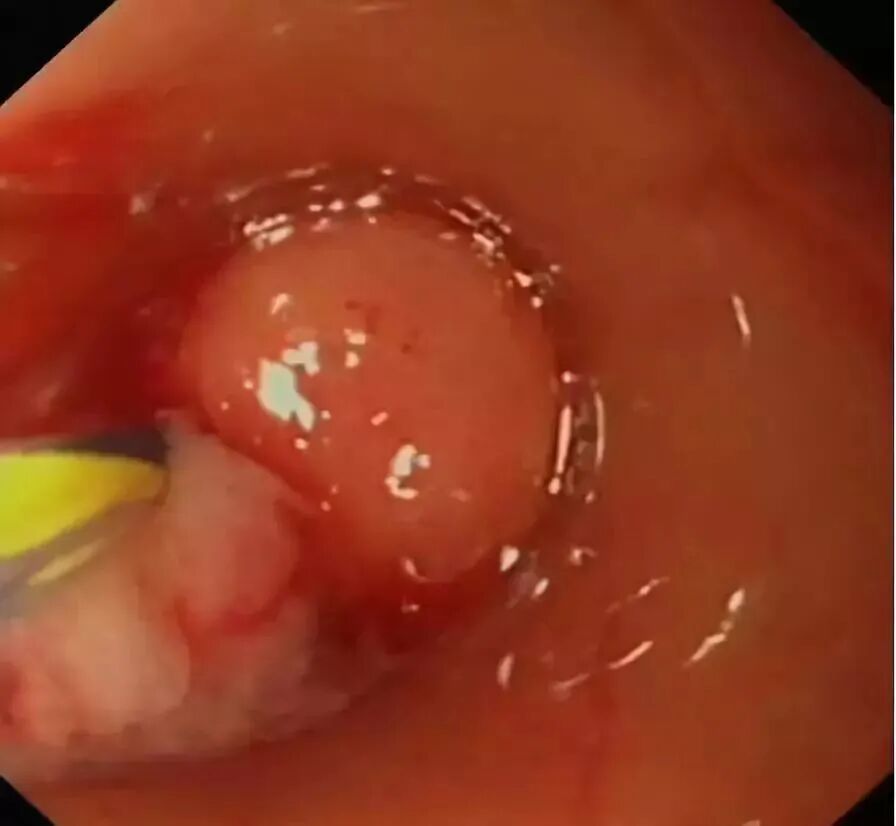

通过内镜下置入球囊导管或取石网篮,将粪石取出,原理如ERCP取石术。(黑箭头示取出的粪石)。

在充分取出粪石后,置入塑料支架行脓液引流及进一步阑尾腔冲洗(生理盐水+抗生素)。